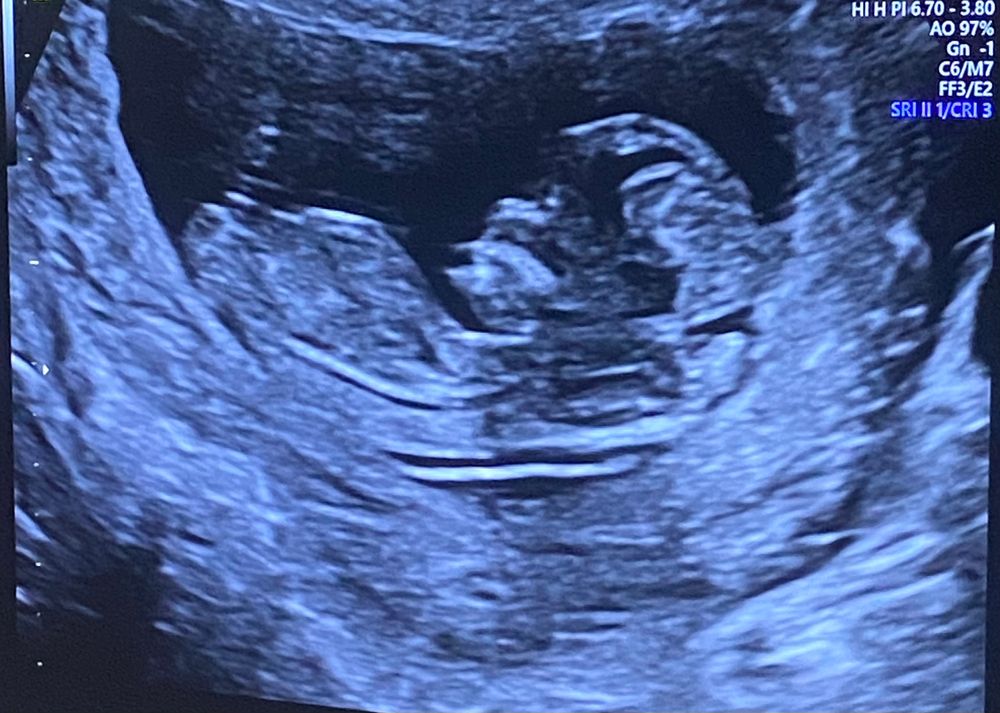

Если так не терпится узнать пол, можно сдать кровь) В 12 недель можно предположить по половому бугорку, но половые органы формируются до 16 недель

Предположу что девочка 🤭🌸

Девочка!!! Вот увидите, девочка там 🌸

Мальчик)

Почти все ошиблись с полом)

Девочка)

Девчуля

Скрининг 1. Определение пола Белок в моче